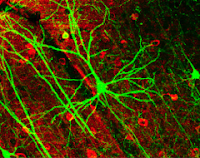

Se sabe que la proteína llamada

netrina ayuda a configurar el sistema nervioso saludable en el cerebro en

desarrollo de un bebé, al dirigir las células cerebrales para que hagan

conexiones apropiadas con otras células cerebrales. La nueva investigación de

los científicos de The Neuro ha descubierto que la netrina en el cerebro adulto

puede fortalecer las conexiones neuronales, lo cual es crucial no solo para aprender

cosas nuevas, sino también para mantener una buena memoria. La liberación

regulada de netrina es esencial para el tipo de cambios sinápticos que subyacen

a los cambios en la neurona que están involucrados en el aprendizaje y la

memoria. Este descubrimiento da un gran paso adelante en la identificación de

cómo el cerebro crea y almacena los recuerdos. La investigación demuestra que

la netrina es fundamental para los cambios en las conexiones entre las células

cerebrales y ofrece un nuevo objetivo

previamente no descubierto para las enfermedades que afectan la función de la

memoria. Los investigadores ahora están realizando experimentos para ver cómo

reaccionan las neuronas cuando se elimina o se les agrega netrina. La investigación

fue publicada en la revista Cell Reports .